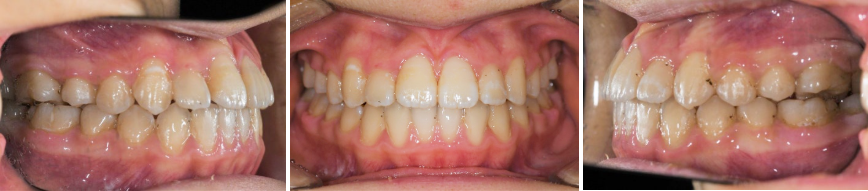

문제점 관찰

이가 고르지 못하며,

덧니들이 있는 모습이 보여집니다

그리고 앞니 하나는 반대로 교합되는 것을 알 수 있습니다.

이대로 두게 된다면,

교합은 잘 맞지 않아서 더 틀어질 것이며

겹쳐진 곳에는 양치질을 잘 해준다 해도

치태와 음식찌꺼기가

남아있을 가능성이 높기 때문에

충치와 치주질환에 더 취약합니다

이를 고르게 펴주어야겠습니다.

이때, 발치를 원하지 않는 경우라면

정밀진단을 한 뒤에 비발치 치아교정으로

계획을 수립할 수 있습니다.